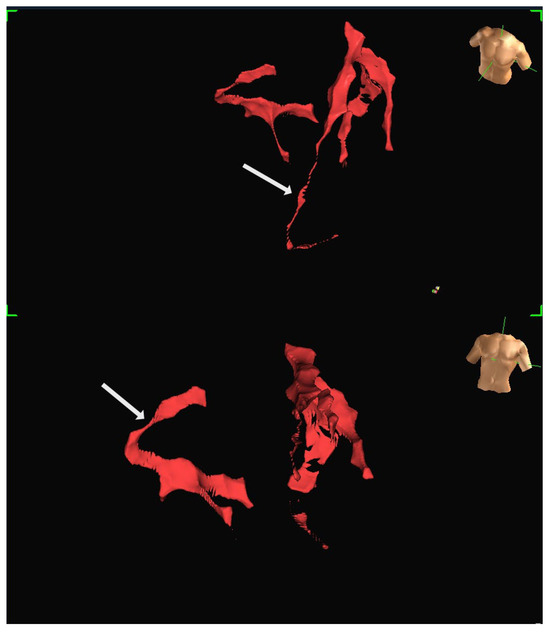

Background: Left ventricular (LV) summit is an important origin for ventricular arrhythmias (VAs). However, the complex electroanatomic structure of LV summit and the surrounding anatomic sites makes ablation of this arrhythmia challenging. Aim: In this paper, we review the main strategies to mapping [...] Read more.

Background: Left ventricular (LV) summit is an important origin for ventricular arrhythmias (VAs). However, the complex electroanatomic structure of LV summit and the surrounding anatomic sites makes ablation of this arrhythmia challenging. Aim: In this paper, we review the main strategies to mapping and ablation of LV summit VAs and summarize our experience in this challenging ablation. Methods: To summarize our experience, we included all consecutive patients with outflow VAs referred to our institute for ablation between 2019 and 2024 who were eventually diagnosed with LV summit origin based on electroanatomical mapping and ablation result using stepwise and sequential ablation approach. Results: A total of 38 patients were found to have VAs from LV summit origin. Overall five patients had history of at least one failed ablation. V1 transition was seen in 15 patients, V2 transition in 12 patients, and V3 transition in 11 patients. Four patients had R wave pattern break in lead V2. Ablation was performed from the earliest activation or from one of the adjacent sites using stepwise and sequential approach. Acute suppression of VAs occurred in 35 patients without complications, except one case of pseudoaneurysm of femoral artery. Conclusions: Stepwise and sequential ablation approach can suppress VAs originating from LV summit in most patients. Full article

Show Figures

Figure 1